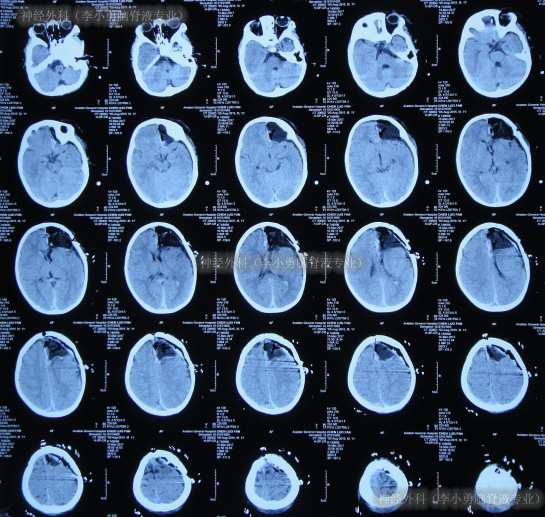

患儿于出生后10月龄即2016年6月1日,患儿意外摔伤头部,在当地的福建省福州市某医院,查头颅CT(图-1)后给予保守治疗后出院观察。

图-1:2016年6月1日头颅CT

但4个月后即2016年10月8日,患儿出现癫痫的症状,第2次就诊于当地的福州市某医院,查头颅核磁(图-2)后诊断为癫痫病灶。

图-2:2016年10月8日头颅核磁

又过5个月,期间患儿癫痫发作变得有所频繁,为求治疗,即2017年3月11日住入北京的某医院,于2017年3月14日,进行了左额颞顶开颅的致痫灶切除术(图-3)。

图-3:2017年3月15日头颅CT

癫痫灶切除术后12天即2017年3月25日,复查头颅CT示癫痫病灶切除术后状态(图-4)。

图-4:2017年3月25日头颅CT

术后24天(2017年4月6日),复查头颅CT(图-5)示“癫痫切除术后现脑积水早期表现”,但未给予处理次日2017年4月7日“出院”。

图-5:2017年4月6日头颅CT